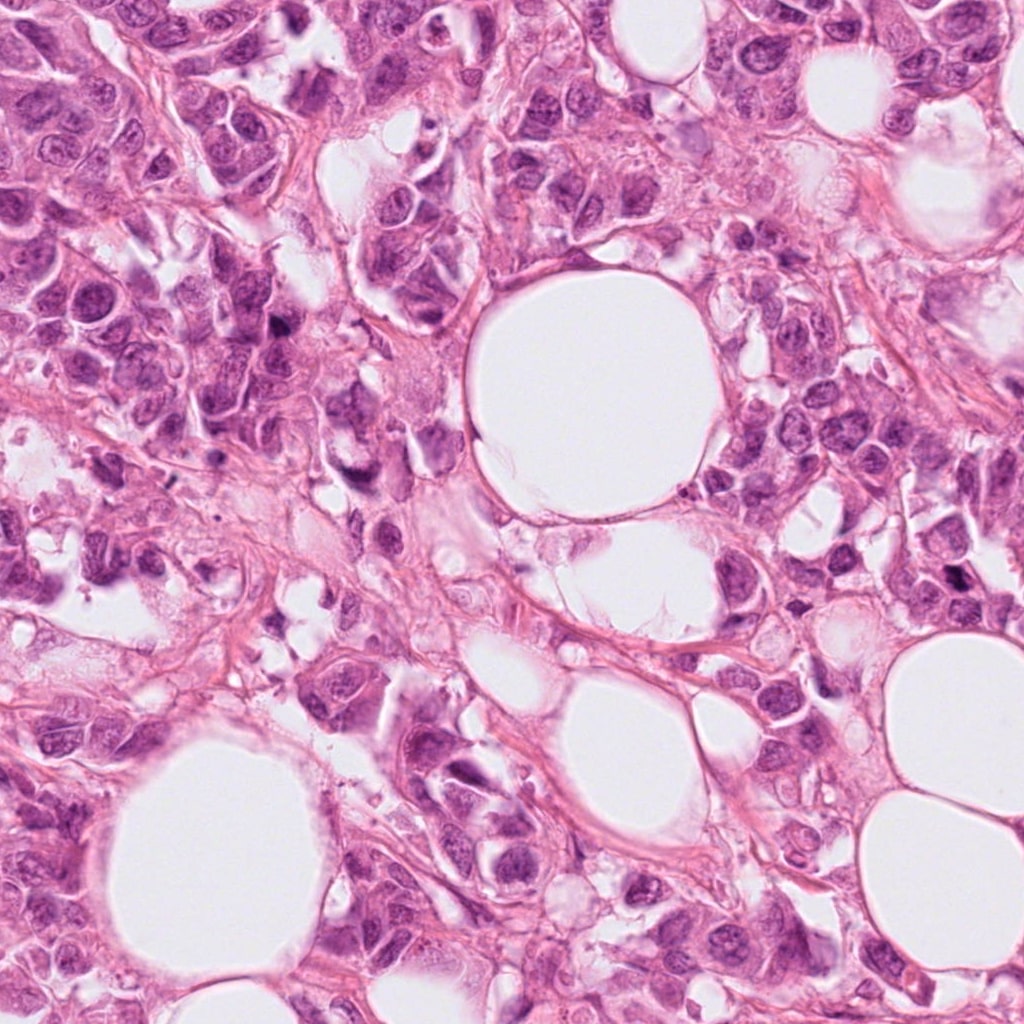

(a) original patch from Hamamatsu XR NanoZoomer 2.0,

Refer to caption

(b) transformed patch for Hamamatsu XR NanoZoomer 2.0

Figure 2: The plots show 1024x1024 patches from original and transformed patches. The domain variability is evident by visual differences in staining in (a), (c), (e), and (f). The transformed patches to the right (b), (d), (f), and (h) respectively shows consistent staining pattern while preserving morphology.